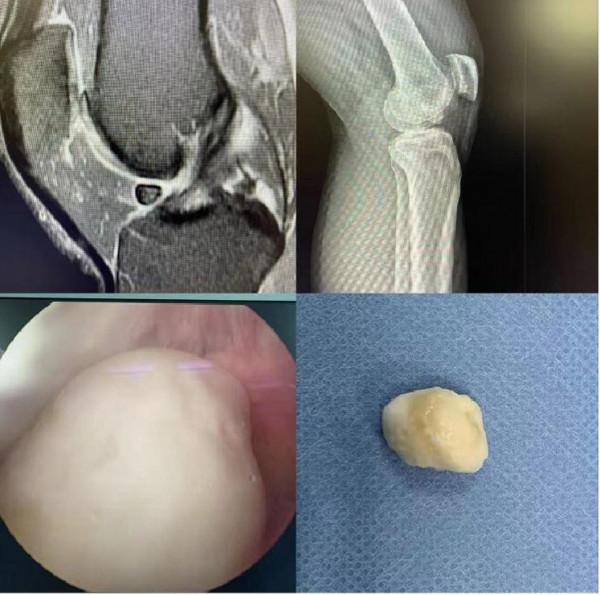

張先生找到了關節中心關節科主任醫師柴生頲,透過詳細的體格檢查,結合膝關節磁共振,發現罪魁禍首原來就是在長期劇烈運動的情況下,左膝關節不斷撞擊,關節軟骨破壞、剝脫後形成的遊離體,最終形成了“關節鼠”,要想徹底改善症狀,就要進行關節鏡手術,將膝關節中產生的遊離體取出。

手術取出遊離體的第二天,張先生髮現無法伸直的膝關節能夠自由屈伸了,沒有了那種術前卡頓的感覺了。經過一段時間的系統的康復訓練,張先生的膝關節將恢復得更好。